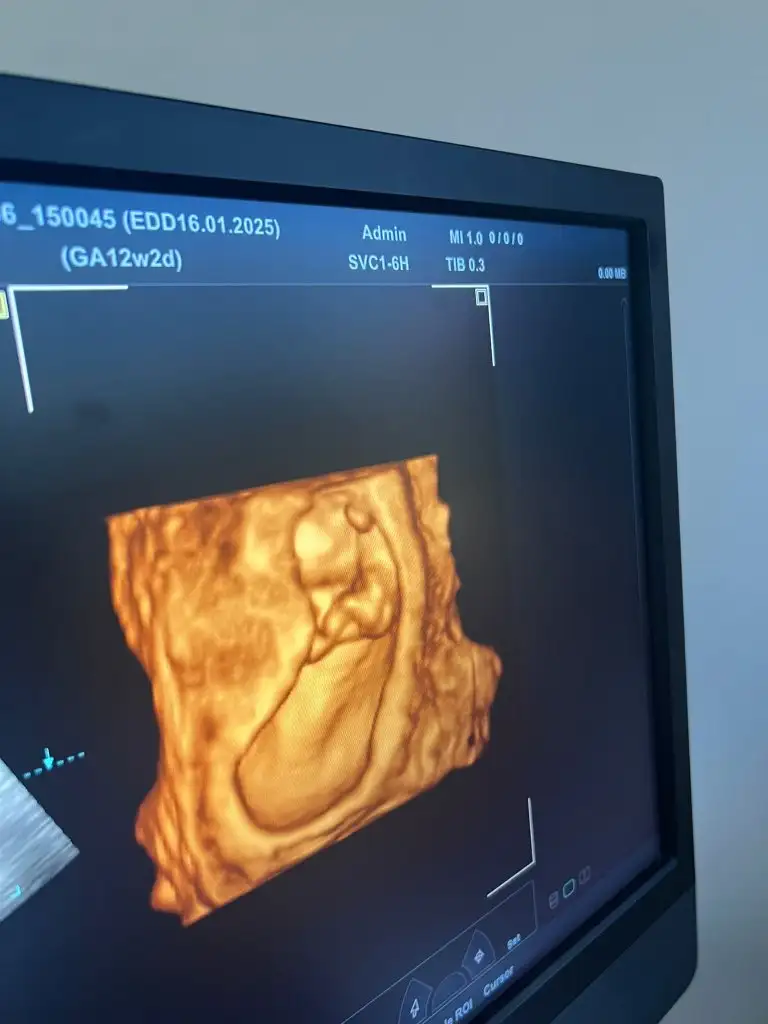

13.haftamızdayız cinsiyet tahminlerinizi yazar mısınız :)🌸

Doktor %70 kız olabilir ama net değil dedi. Benimde hep içimde kız vardı taaaki bu ultrasona kadar. Nedensebu ultrasonda erkek hissettim. ☺

Allah gönlünüze göre versin inşallah bana da yüzde 70 kız gibi dedi bu cumartesi gidince net belli olacak 3 kızım var buda erkek olsa fena olmaz ama kız gibi geliyor bana da hayırlısı olsun tabi öncelikle sağlıklı olması 🥰